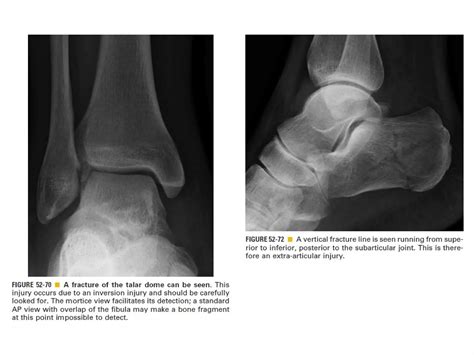

Skeletal trauma | PPT